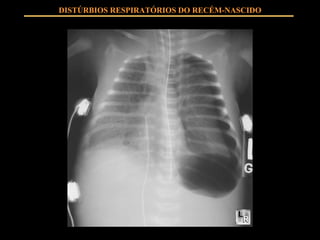

DISTÚRBIOS RESPIRATÓRIOS DO RECÉM-NASCIDO USO DE SURFACTANTE EXÓGENO: Diminui tensão superficial alveolar Mantém estabilidade alveolar

DISTÚRBIOS RESPIRATÓRIOS DO RECÉM-NASCIDO USO DE SURFACTANTE EXÓGENO: PROFILÁTICO RESGATE

DISTÚRBIOS RESPIRATÓRIOS DO RECÉM-NASCIDO USO DE SURFACTANTE EXÓGENO: DISTRESS RESPIRATÓRIO GRAVE EM PRIM 48 HS ADMINISTRAÇÃO ASSIM QUE DIAGNÓSTICO O USO DE SURFACTANTE É SEGURO É UM A TERAPIA DE ALTO CUSTO